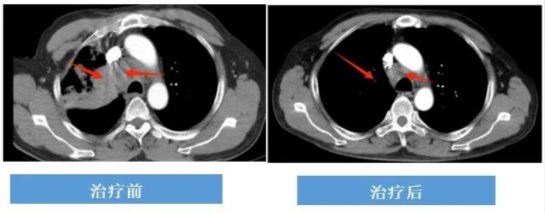

无驱动基因突变晚期肺鳞癌:免疫治疗+化学治疗